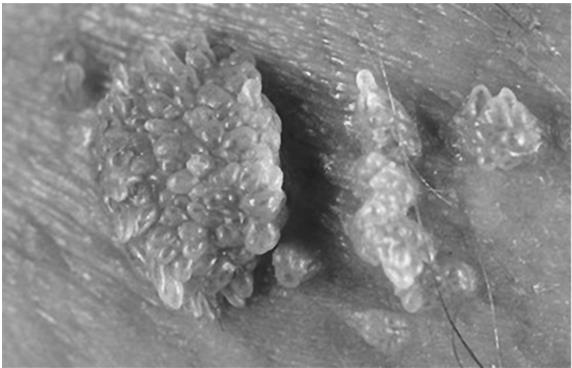

Кондиломы появляются исключительно на слизистых оболочках, в области промежности, вульвы, влагалища, на шейке матки, в области анального отверстия и вокруг него, в анальном канале, а также в ротовой полости. Внешне они могут быть единичными – в виде остроконечных выростов розового, белесоватого, серого, коричневого цвета, а также многоцветными. Часто они образуют скопления с сосочковыми разрастаниями. Такие образования могут напоминать цветную капусту или петушиный гребень. Плоский вариант кондилом выглядит как небольшие возвышающиеся над кожей образования с бугристой поверхностью различной окраски.

Иллюстрация к книге — В зоне риска. Тонкости защиты женского организма. Как ВПЧ проникает в наш организм, чем он опасен и что поможет избежать последствий [i_030.jpg]

ВИД КОНДИЛОМ